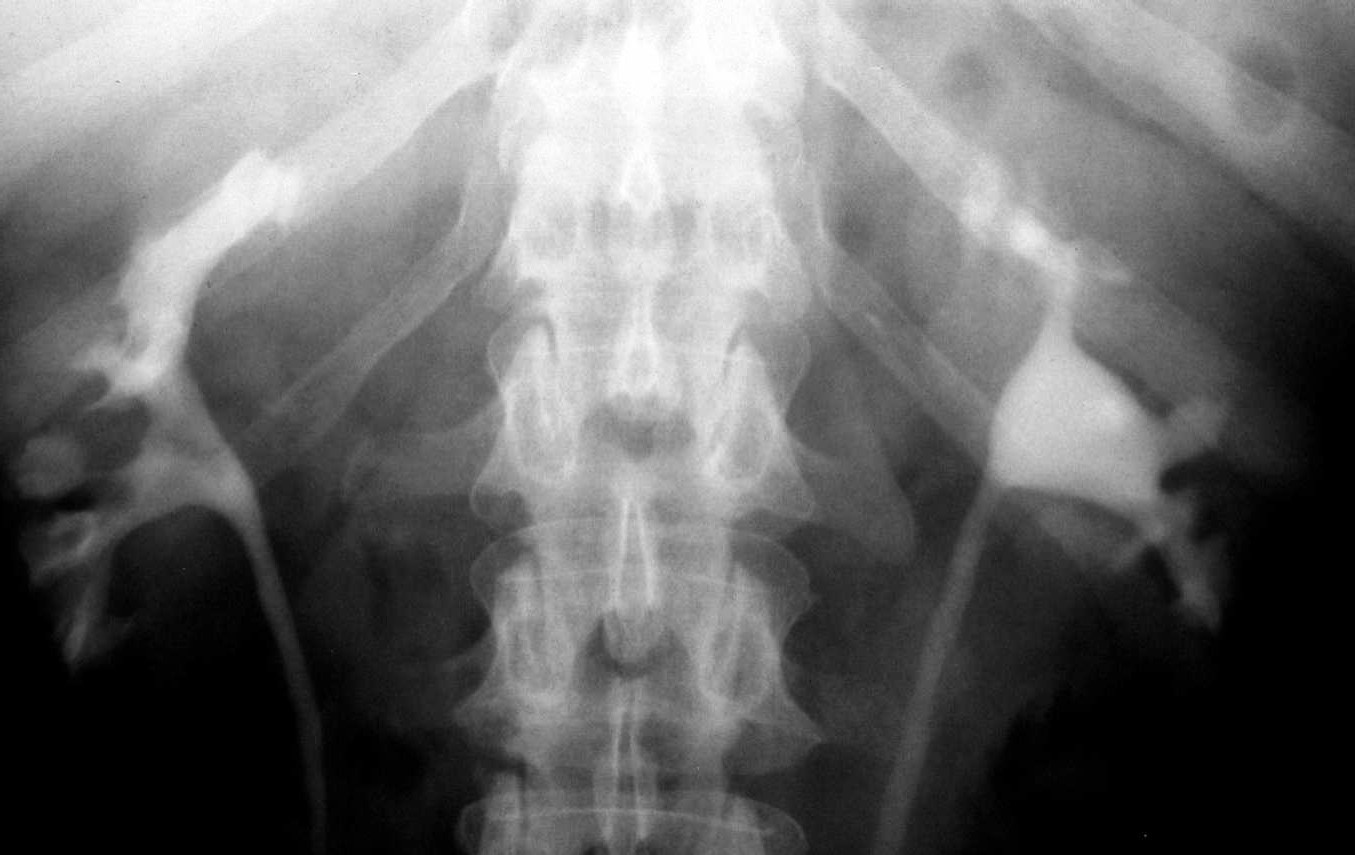

- Figure 6: IVP showing hydronephrosis due to ureteric TB